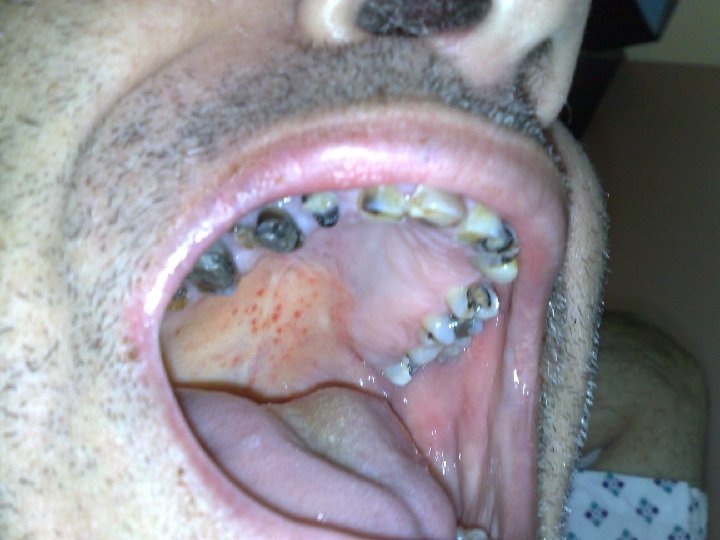

Autres infections • Cardio-vasculaires • Neuro-méningées • Autres : – Endophtalmies – Stomatologiques –…

Expression clinique • L’affection est strictement liée au SNC • présence de lésions herpétiques orales ou faciales rarement constatée (moins de 10%) n’a pas de valeur particulière. . • Aucun signe pathognomonique, examens complémentaires nécessaires.